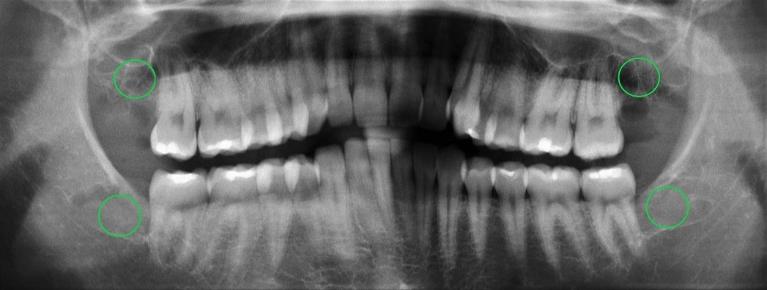

• You have wisdom teeth coming in at odd angles or crowding other teeth.